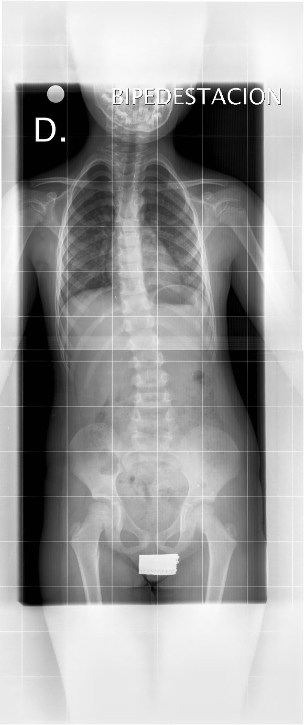

TELERRADIOGRAFÍAS DE LA COLUMNA VERTEBRAL SIN PATOLOGÍA

Aparte de valorar la situación del raquis, las telerradiografías de la columna vertebral aportan información muy importante relativa a la madurez esquelética. La presencia o no de algunos núcleos de osificación o la osificación de otras zonas cartilaginosas nos permite sopesar la posibilidad de progresión de una curva en función del crecimiento remanente. El cartílago trirradiado, abierto o no, así como el grado de osificación del núcleo de osificación de la cresta iliaca, llamado test de Risser y definido en 5 estadios, son aspectos muy importantes que hay que valorar en una escoliosis (Figura 3). El test de Risser nos ayuda a valorar la maduración esquelética, la previsión de crecimiento, si ha pasado la fase de aceleración del crecimiento. Por eso, la necesidad de visualizar la pelvis completa en esta exploración radiográfica.

Figura 3. Esquema del test de Risser. Mostrar/ocultar